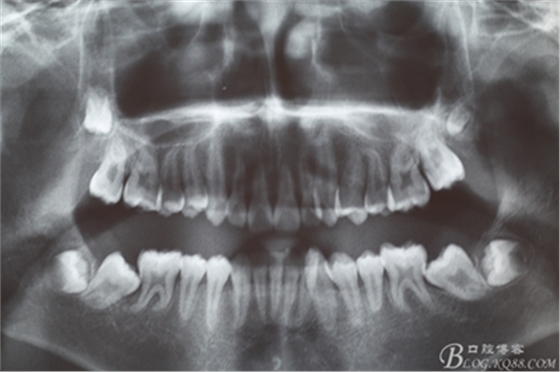

圖1.術(shù)前患者的全景片檢查:38、48牙冠已經(jīng)形成,牙冠方向?yàn)樗轿唬?7、38近中位萌出。